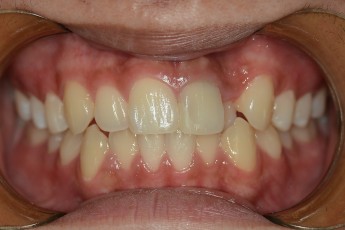

Before

After